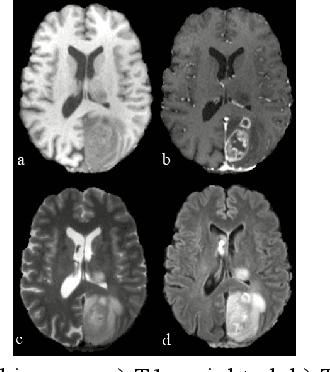

Abstract:Deformable image registration is a key task in medical image analysis. The Brain Tumor Sequence Registration challenge (BraTS-Reg) aims at establishing correspondences between pre-operative and follow-up scans of the same patient diagnosed with an adult brain diffuse high-grade glioma and intends to address the challenging task of registering longitudinal data with major tissue appearance changes. In this work, we proposed a two-stage cascaded network based on the Inception and TransMorph models. The dataset for each patient was comprised of a native pre-contrast (T1), a contrast-enhanced T1-weighted (T1-CE), a T2-weighted (T2), and a Fluid Attenuated Inversion Recovery (FLAIR). The Inception model was used to fuse the 4 image modalities together and extract the most relevant information. Then, a variant of the TransMorph architecture was adapted to generate the displacement fields. The Loss function was composed of a standard image similarity measure, a diffusion regularizer, and an edge-map similarity measure added to overcome intensity dependence and reinforce correct boundary deformation. We observed that the addition of the Inception module substantially increased the performance of the network. Additionally, performing an initial affine registration before training the model showed improved accuracy in the landmark error measurements between pre and post-operative MRIs. We observed that our best model composed of the Inception and TransMorph architectures while using an initially affine registered dataset had the best performance with a median absolute error of 2.91 (initial error = 7.8). We achieved 6th place at the time of model submission in the final testing phase of the BraTS-Reg challenge.